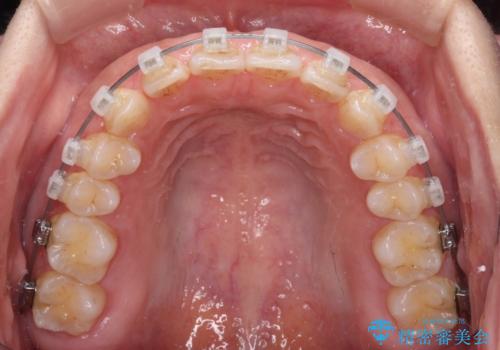

【モニター】ディープバイトを治す ワイヤー装置による矯正治療

- クリアブラケット

- 顎が疲れるほどのディープバイトを気にして来院された患者様です。

手前に傾斜している奥歯を直立させながら、歯列全体の平面を均一に整えることでディープバイトを改善していくこととしました。

ディープバイトは咬合力が強いことが特徴であり、より良い仕上がりとするために、臼歯部のコントロールを行いやすいワイヤー装置を用いて矯正治療を行うこととしました。